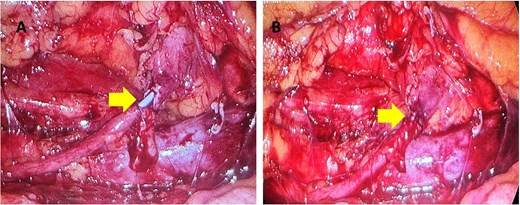

One month later a laparoscopic repair of the RU was completed. Under general anaesthetic the patient was placed right side up. A pneumoperitoneum was created with the Kii Fios first entry system and a 5 mm camera, two additional ports were used (5 mm and 12 mm). The ascending colon was mobilized medially and the IVC identified. Careful dissection allowed identification of the RU (Fig. 4). The ureter was fully mobilized behind the IVC, then divided and spatulated. Two 4.0 vicryl stay sutures were used to anastomose the apex of the spatulated ureter to proximal ureter. The posterior uretero-ureteral anastomosis was performed with interrupted 4.0 vicryl sutures. A 6 French (Fr), 24 cm JJ stent was placed into the ureter and the anterior anastomosis was performed again with interrupted 4.0 vicryl sutures (Fig. 5A and B). A 16Fr non-suction drain and a 16Fr urinary catheter were placed.

(A, B) The yellow arrow is pointing to incomplete uretero-ureteral anastomosis. The blue JJ stent is visible. In Fig. 5(B) the anastomosis is complete.